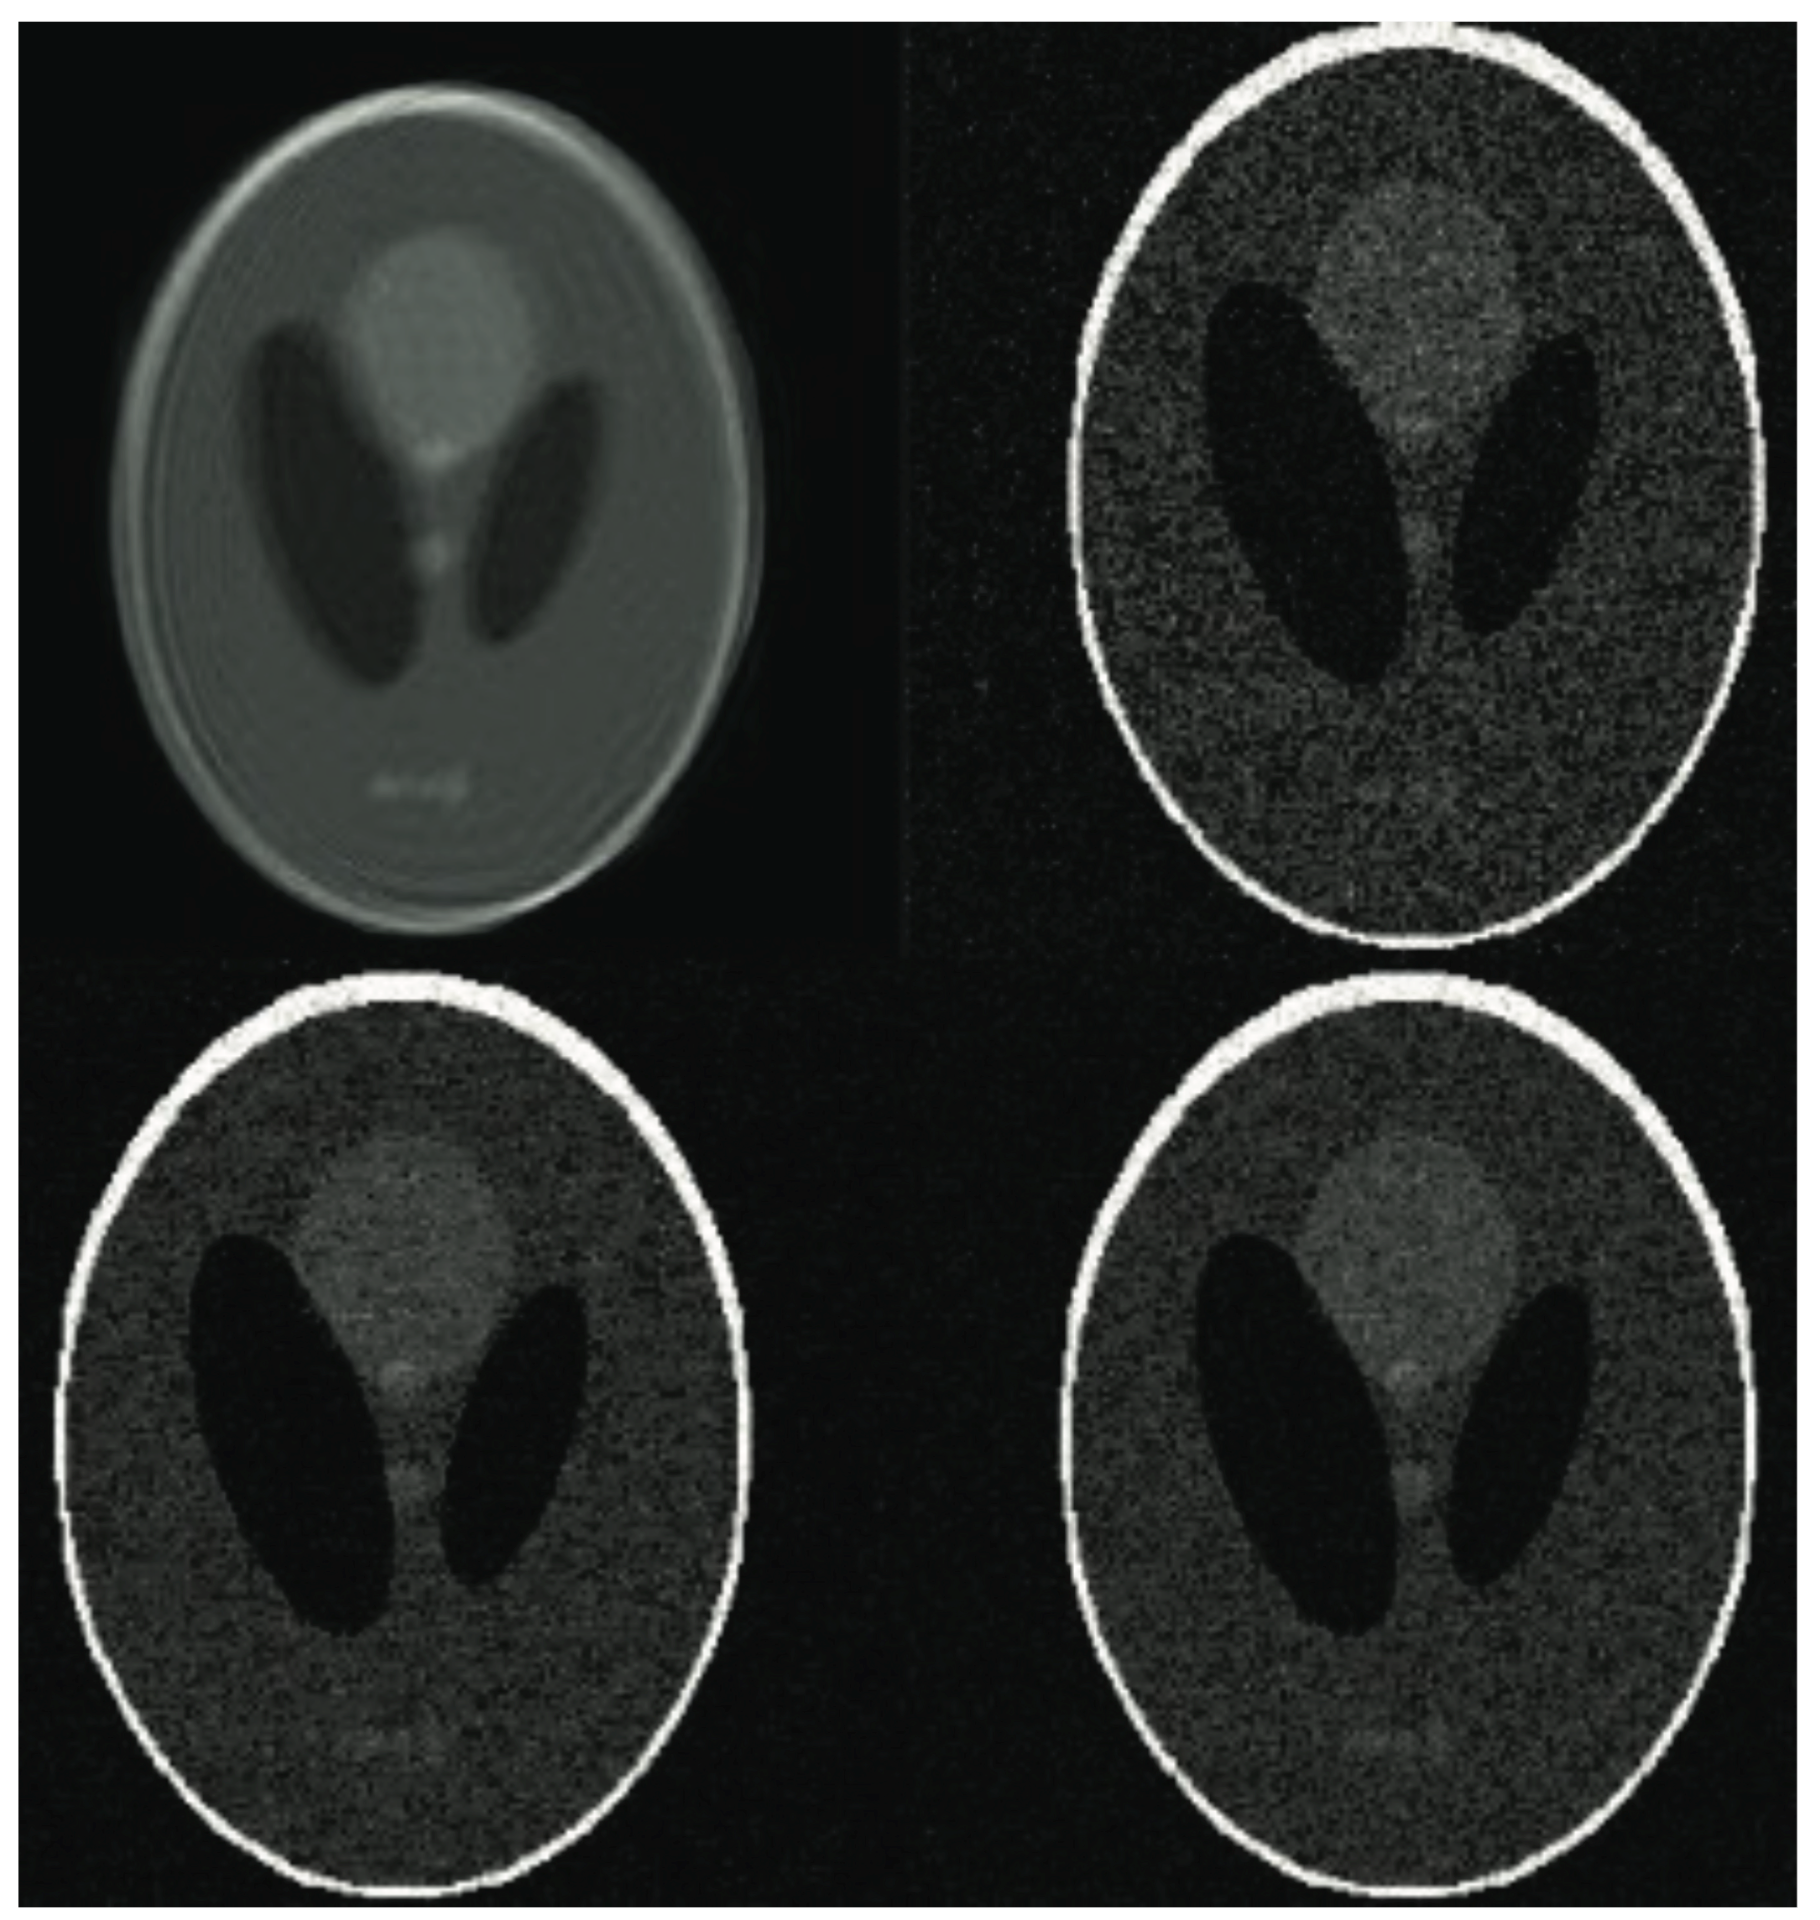

Figure 8. The abdominal image processing. From left to right: A: Image reconstructed from partially sampled PROPELLER blade, B:Cartesian sampling grid without image registration applied (with no downsampling applied), C: B-spline Cubic interpolation, D: Non-Rigid Multi-Modal 3D Medical Image Registration Based on Foveated Modality Independent Neighbourhood Descriptor [45], E: Enhanced deep residual networks for single image super-resolution [14], F: Image super-resolution using very deep residual channel attention networks [16], G: Residual dense network for image super-resolution [15], H: super-resolution with proposed sampling scheme and motion compensation (the proposed algorithm). Compression ratio is 50%. Please see Table 3 for the PSNR values at other compression ratios.